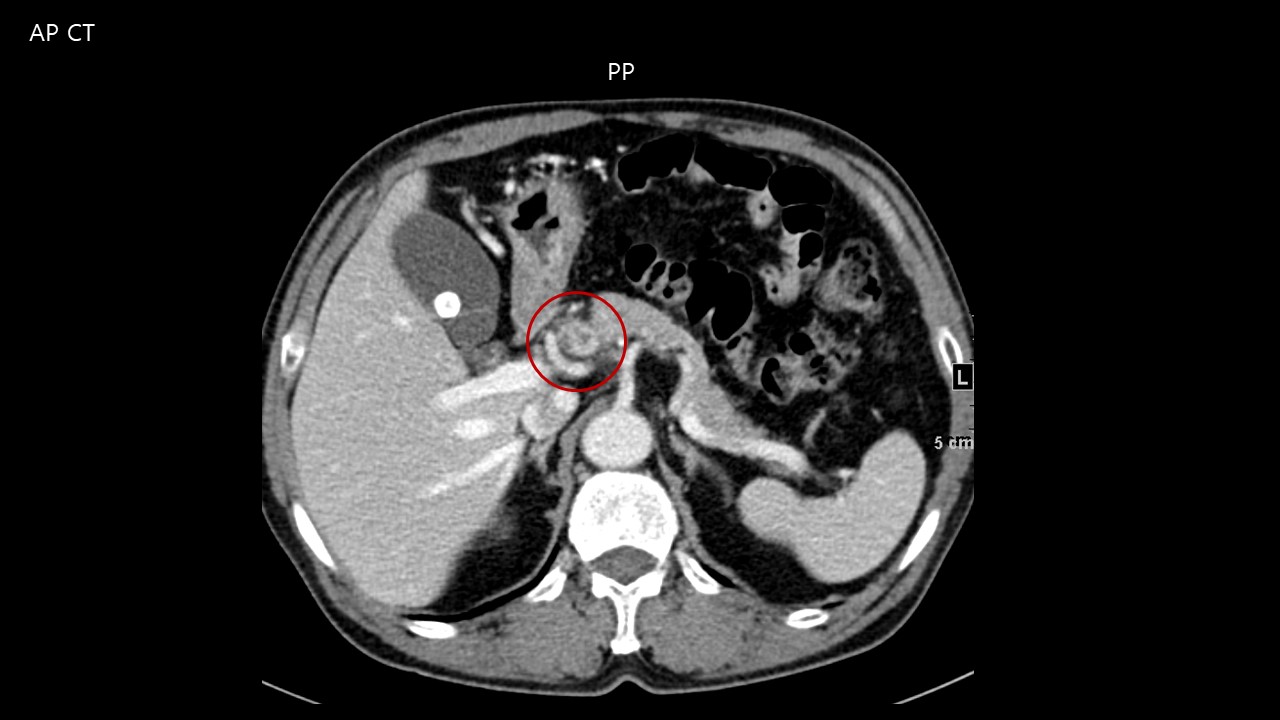

Case

No.723

M / 58

Peripancreatic mass

ABDOMEN

±¹¸³¾Ï¼¾ÅÍ À̹ÎÈñ

CASE2

27